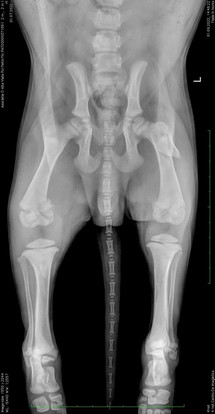

Die Diagnose lautete, neben etlichen schmerzhaften Prellungen: Oberschenkelbruch des linken Hinterlaufs!

Otto konnte erfolgreich operiert werden und befindet sich nun bei Gabriela zu Hause, denn es bedarf hier einer intensiven Pflege und Nachsorge, die im Shelter nicht gewährleistet werden kann.